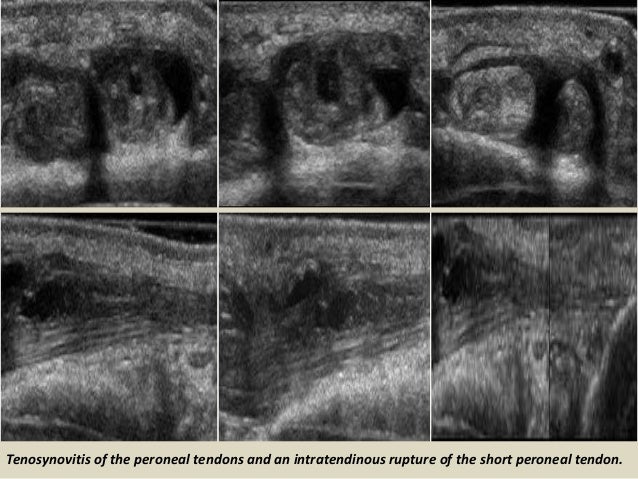

Tenosynovitis of the peroneal tendons and an intratendinous rupture of the short peroneal tendon.

47. 47. Tenosynovitis of the peroneal tendons and an intratendinous rupture of the short peroneal tendon.